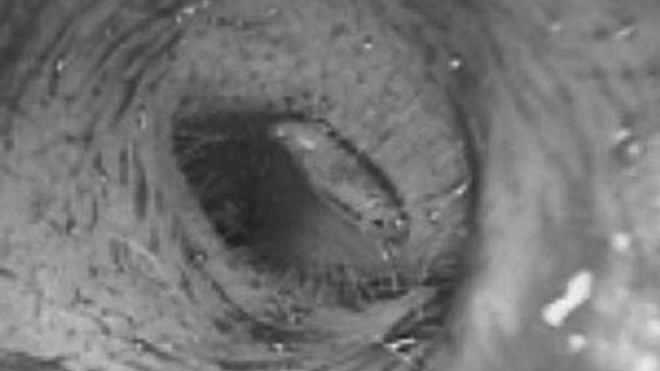

Ấu trùng ruồi trong lỗ tai (ảnh: Dân trí)

Vào ngày 8/12, bệnh nhân T.V.S. (trú xã Phong Bình, huyện Phong Điền, tỉnh Thừa Thiên – Huế) đã nhập viện ở BV Trung ương Huế với tai trái đau và nhức, có chảy dịch màu nâu hôi, riêng ống tai bị phù nề. Các bác sĩ của Khoa Tai - Mũi - Họng đã phát hiện trong tai trái của bệnh nhân S. có ấu trùng ruồi đang bò trong ống tai.

Trong tối cùng ngày 8/12, êkíp mổ gồm BS CK II Hồ Mạnh Hùng, Phó Trưởng khoa Tai - Mũi - Họng, BS CK II Đặng Như Quang (khoa Gây mê B) và BS nội trú Ngô Đức Lưu đã thực hiện ca mổ thành sau ống tai. Kết quả, ca mổ đã thành công, toàn bộ các ấu trùng ruồi đang sống được lấy hết ra khỏi tai bệnh nhân S.